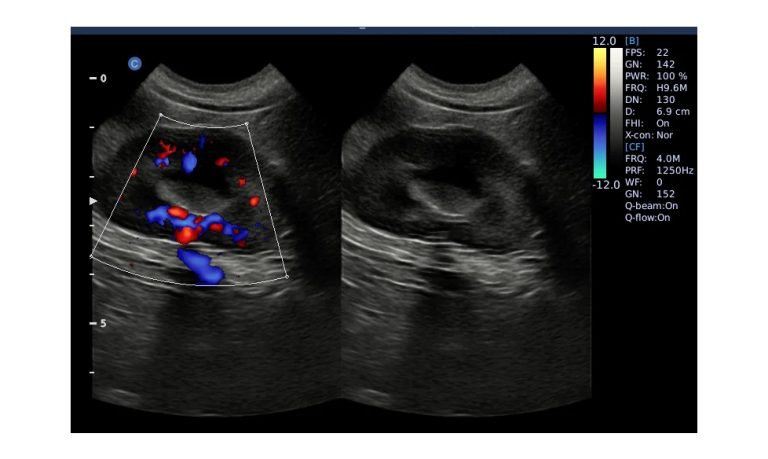

ECO5 VET

Ultra-Portable, Ultra- Affordable, Color doppler

The multi-purpose user presets, comprehensive measurement & report system, built-in EasyView image achieve system, quick image storage / retrieve / transfer, one-button direct print, make the complete workflow better than what you can dream of.